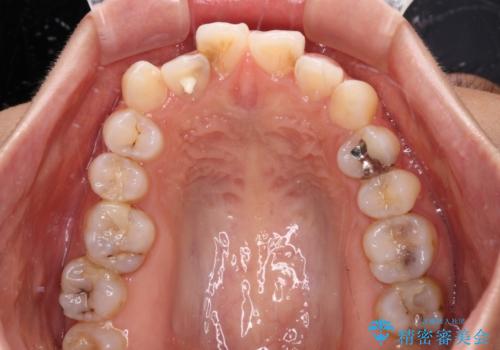

- 前歯のデコボコと口元の突出感を気にして来院された患者様です。

口元の突出感が認められ、更には左右で異なる咬合状態であったため、下顎右側は第二小臼歯を、左側は第一小臼歯を抜去することでバランスを取るような治療計画としました。

また上顎前歯は大臼歯に補綴治療が必要であったため、矯正治療後にオールセラミッククラウンによる補綴治療を行うこととしました。

下顎の抜歯位置を左右で変えることで、最終的に上下正中をほぼ一致させることができました。